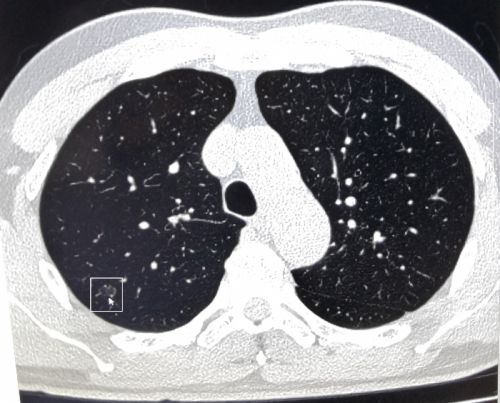

张先生体检时肺部ct筛查影像显示有可疑结节(箭头处)。

复查肺穿刺活检,确诊张先生为早期“微小浸润性肺腺癌”。

近日,长沙57岁的张先生到捷克论坛 岳麓山院区健康管理中心做健康体检时提出,胃肠道有些不适,想做胃肠镜等项目。中心主任李慧根据其咳嗽症状、吸烟史和年龄等因素,建议增加肺部CT项目。张先生觉得没必要,经过李慧主任耐心解释后欣然接受,结果CT显示“右上肺可见大小约8×6mm结节”,建议跟踪复查,每半年一次。

李慧主任看了检查结果后非常重视,要求中心回访医生缩短标准回访跟踪间隔时间。一个月后,工作人员进行电话回访时,建议张先生到健康管理中心肺结节门诊就诊。看门诊时,医生给张先生复查了低剂量高清晰肺部增强CT,显示右上肺结节较上次变大,立即安排肺穿刺活检,确诊为“早期微小浸润性肺腺癌”。幸运的是,由于回访跟踪及时,尚属肺癌早期。住院做了根治手术后,张先生目前状态良好。